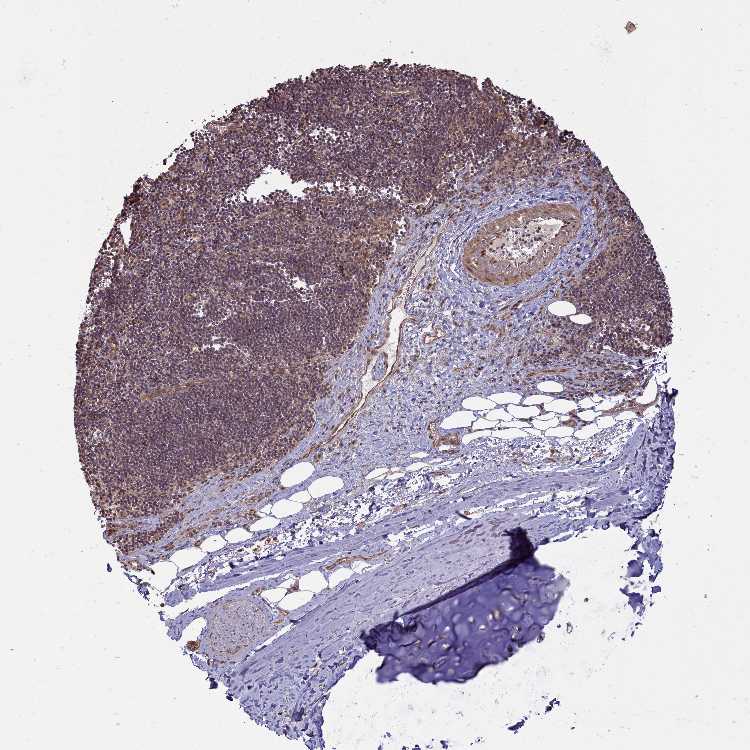

SOFT TISSUE 1 - Antibody stainingi

Antibody staining in the annotated cell types in the current human tissue is reported as not detected, low, medium, or high, based on conventional immunohistochemistry profiling in selected tissues. This score is based on the combination of the staining intensity and fraction of stained cells.

Each image is clickable and will lead to virtual microscopy that enables deeper exploration of all samples and also displays staining intensity scores, fraction scores and subcellular localization as well as patient and tissue information for each sample.

Antibody HPA041188

Chondrocytes Medium

Fibroblasts Not detected

Peripheral nerve Low